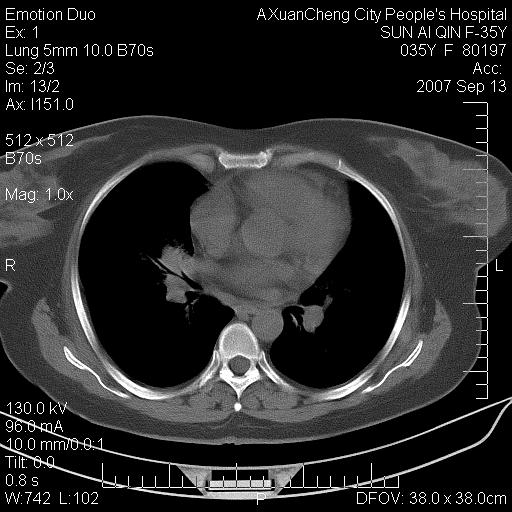

以下是引用天南地北在2007-9-13 13:43:00的发言:[br]考虑双肺、肺门侵润

以下是引用ydx_74在2007-9-13 15:42:00的发言:[br]仅看片,考虑右上肺癌并双肺转移,结合病史,考虑肺门、肺内淋巴侵润

以下是引用同在2007-9-13 15:08:00的发言:[br]支持肺门及双肺侵润.